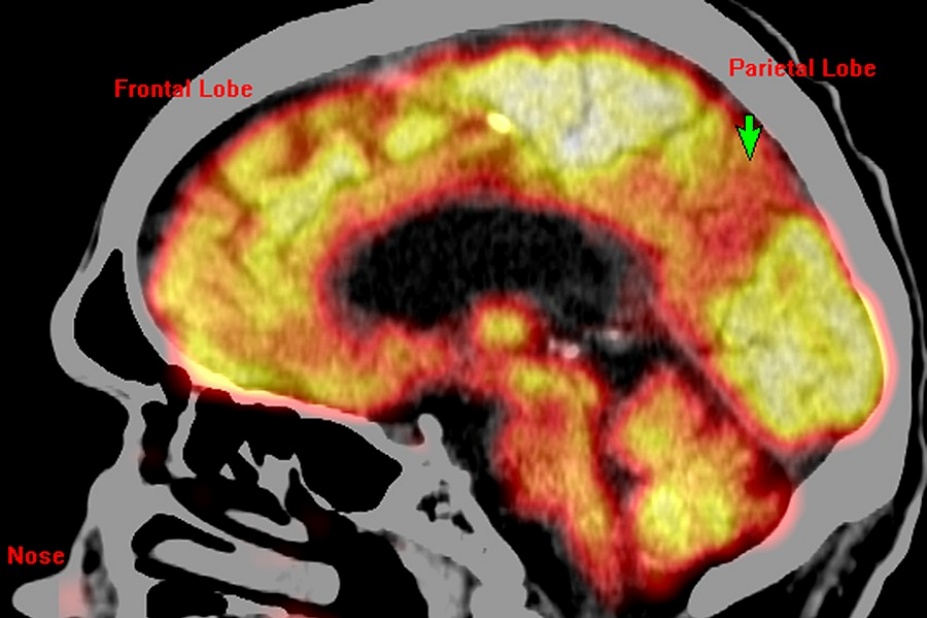

Image of glucose metabolism PET overlaid on CT in an Alzheimer's patient with mild dementia. Green arrow points to regional hypometabolism in the medial parietal lobe, (which processes biographical information and memory),a proposed biomarker for Alzheimer’s. (Credit: UB Center for Positron Emission Tomography)

Miletich said that nuclear medicine techniques exist to reveal both general regional physiology, such as glucose metabolism or blood perfusion, and specific neurochemical physiology, such as the status of the brain dopamine system. Such information is useful in the care of patients with disorders ranging from strokes to dementia.

Miletich relies on SPECT and PET/CT because these techniques reveal different patterns of physiology. These patterns are both sensitive and specific for many brain disorders.

“There are cases, such as in traumatic brain injury, where commonly used techniques, like CT and MRI show no abnormalities, but where a patient continues to be profoundly compromised in his or her daily life,” he said. “In those cases, cerebral perfusion SPECT and glucose metabolism PET/CT can reveal exactly where in the brain the injury is located and the extent of damage to the brain.

“When I image the brain with SPECT or PET/CT, I can see disorders long before they have fully developed. I can see Alzheimer’s before the patient has dementia. This will facilitate the development of abortive therapy for Alzheimer’s,” said Miletich.